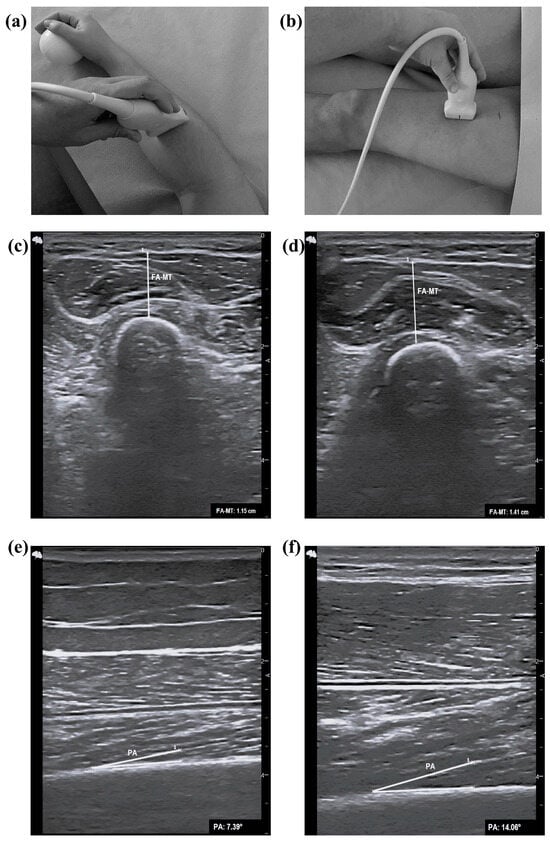

2.5. Assessment of Ultrasound Parameters

| FA-MT (cm) | |||||||

| Men | 0.796 | 0.554–1.038 | 0.017 | 0.714 | 0.143 | 0.571 | 1.41 |

| Women | 0.710 | 0.509–0.910 | 0.041 | 0.516 | 0.000 | 0.516 | 0.94 |